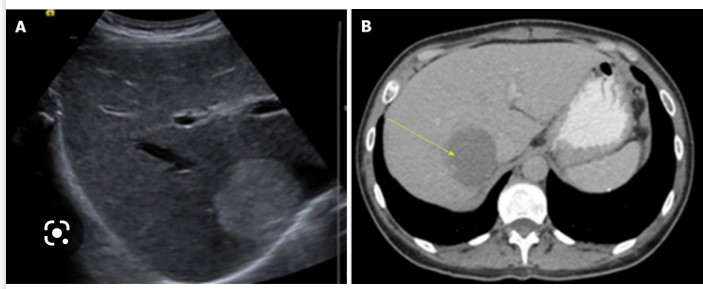

영상검사: 간단히 복부 초음파를 통해 덩어리를 발견하거나 이보다 더 정밀한 검사로 CT (컴퓨터 단층 촬영), MRI (자기 공영 명상), 99mTc-RBC scan (테크네슘-적혈구 스캔) 검사가 있습니다. 이런 방법으로 진단할 수 없는 경우에는 조직 검사나 혈관 조영술을 시행합니다. 의심 소견이 나올 경우에는 임상 추적 관찰이 매우 중요합니다.